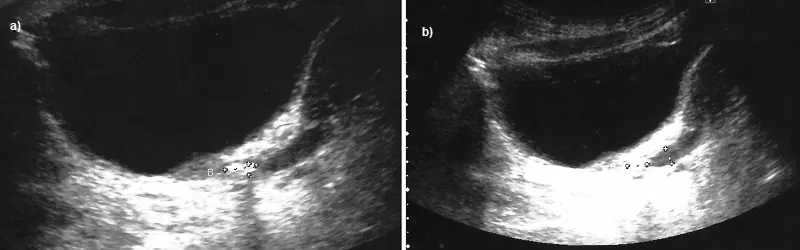

W powtórzonym badaniu USG, zaprezentowanym na rycinie 7, uwidoczniono złóg lub konglomerat drobnych złogów o wymiarach 8 x 3 mm w przypęcherzowym odcinku prawego moczowodu w odległości około 1 cm od pęcherza oraz powyżej niego widoczny poszerzony moczowód szerokości 6–8 mm. W kielichach środkowych nerki prawej uwidoczniono złóg wielkości 5 mm.

Ryc. 7. Obraz USG z a) widocznym złogiem/konglomeratem złogów w przypęcherzowym odcinku moczowodu i b) z poszerzeniem moczowodu powyżej złogu